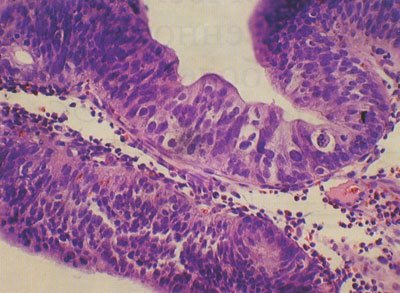

Ворсинчатая аденома (папиллома, железисто-ворсинчатый полип) - доброкачественная опухоль, напоминающая цветную капусту, очень мягкой консистенции, нередко достигает больших размеров и циркулярно охватывает просвет кишки.

Опухоль отличается от тубулярной аденомы, описанной выше, своим видом и клиническими проявлениями. Ворсинчатая аденома обычно не имеет ножки, сидит на широком основании, по структуре напоминает дольчатую губку и кровоточит при малейшем прикосновении. Иногда ворсинчатая опухоль не имеет резко очерченной формы, она как бы расползается на поверхности слизистой оболочки толстой кишки.